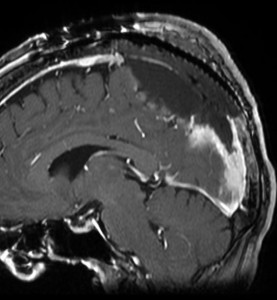

上矢状洞髄膜腫 superior sagittal sinus meningioma

また別な例です。1986年13歳の時に2度の開頭手術を受けましたが,全摘出できずにそのまま経過観察されました。

左の画像は1997年の術前のものです。これを2回に分けて全摘出しました。上矢状洞はやはり冠状縫合のあたりから静脈洞交会まで摘出しました。その下の大脳鎌も全て摘出したので,直静脈洞の上壁を開けることになり,直静脈洞からの激しい出血があり縫合して直静脈洞形成をするのが大変でした。手術後16年が経過しますが再発していませんし,社会人として普通に暮らせています。

この例が教えてくれることは,上矢状静脈洞は全長にわたり切除してしまっても,神経脱落症状を出さないで普通に生きて行かれるということです。